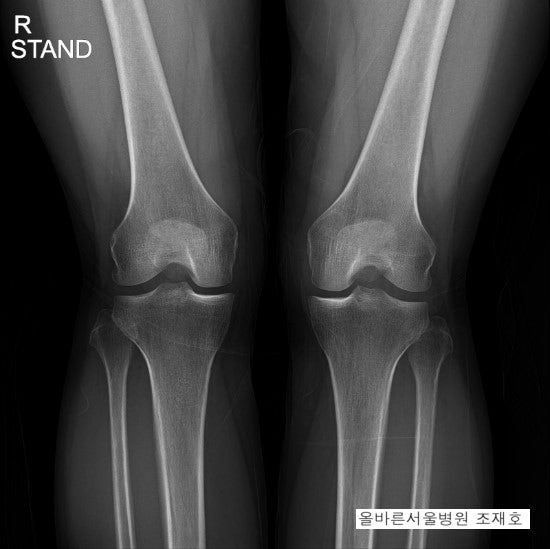

무릎 통증을 호소하며 광주 운암동 정형외과를 찾는 환자들은 다양한 질환을 가지고 있습니다. 무릎 통증을 유발하는 질환은 매우 다양합니다. 통증이 발생하는 부위에 따라 어떤 질환인지 진단할 수 있지만 무릎 앞에 통증이 있다면 슬개골 연화증이나 점액낭염을 의심해 볼 수 있습니다. 반대로 무릎 바깥쪽에 통증이 있는 경우에는 외측 인대, 외측 연골판이 파열되면서 발생한 통증이거나 장경부인대증후군이 원인일 수 있습니다.

또 무릎 뒤에 통증이 발생하게 되면 후방 십자인대가 파열될 가능성, 또는 슬와낭종으로 인한 물집이 생겨 통증이 생긴 경우 혹은 후각부가 파열되면서 생긴 통증일 수 있습니다. 내무릎 통증이라면 안쪽 인대, 안쪽 연골판이 손상됐을 가능성도 있고 골연골 손상으로 퇴행성 관절염이 발병한 것은 아닌지 의심해 볼 수 있습니다. 이러한 통증은 나이나 성별에 관계없이 누구에게나 발병할 수 있습니다. 따라서 평소에도 이 통증이 지속적으로 느껴진다면 반드시 무시하지 말고 잘하는 광주 운암동 정형외과를 찾아 내원하는 것이 좋습니다.

이러한 통증의 공통적인 원인은 무릎 연골이 퇴화하는 것입니다. 오랜 사용으로 연골이 소실된 경우 인공관절을 이식할 필요가 있는 경우도 있습니다. 하지만 빠른 내원으로 조기에 증상을 발견하고 완전한 소실 전 치료를 시작할 수 있거나 연골 손상이 심각하지 않은 중기 단계 환자라면 인공관절을 이식하지 않고도 수술치료를 통해 해결이 가능합니다. 이 수술은 카르티스템 줄기세포 이식술입니다. 카르티스템은 원래 줄기세포를 치료하는 데 필요한 골수나 지방이 필요한 일반적인 시술과 달리 본인이나 다른 지인에게 채취되지 않아도 진행이 가능하다는 장점이 있습니다.이러한 통증의 공통적인 원인은 무릎 연골이 퇴화하는 것입니다. 오랜 사용으로 연골이 소실된 경우 인공관절을 이식할 필요가 있는 경우도 있습니다. 하지만 빠른 내원으로 조기에 증상을 발견하고 완전한 소실 전 치료를 시작할 수 있거나 연골 손상이 심각하지 않은 중기 단계 환자라면 인공관절을 이식하지 않고도 수술치료를 통해 해결이 가능합니다. 이 수술은 카르티스템 줄기세포 이식술입니다. 카르티스템은 원래 줄기세포를 치료하는 데 필요한 골수나 지방이 필요한 일반적인 시술과 달리 본인이나 다른 지인에게 채취되지 않아도 진행이 가능하다는 장점이 있습니다.카르티스템은 채취가 필요 없도록 만들어진 치료제로 연골 부위에 주입해 무릎 내부의 손상된 연골을 재생시키는 전문의약품입니다. 이 치료제는 제대혈의 혈관인 제대혈을 재료로 만든 치료제로 제대혈 속에 있는 간엽 줄기세포를 추출한 것입니다. 이 줄기세포는 연골과 같은 구성분을 이루고 있기 때문에 연골 재생 촉진이 가능합니다. 무릎 연골을 카르티스템 치료제를 주입하여 재생시키는 방법은 부작용 걱정도 줄일 수 있습니다. 이 시술법의 안전성을 확인하기 위해 3단계 임상시험을 거쳤을 뿐만 아니라 식약처 약사법 허가를 받아 안전성과 유효성을 승인, 검증된 의약품이며 광주 운암동 정형외과의 오랜 시술 경험과 노하우를 바탕으로 숙련된 의료진이 직접 상담부터 수술과정까지 맡아 치료하기 때문에 과정 중 발생하는 부작용이나 문제 등을 걱정하지 않아도 됩니다.이 수술법은 통증 완화 기능뿐만 아니라 무릎 통증을 일으킨 질환의 진행 속도를 늦추는 역할도 해 환자에게 다방면에서 도움이 되는 치료법입니다. 카테스템을 이식해 치료를 시작한 지 6주 정도 지나면 연골 분화가 나타나고 1년 정도 지나면 연골 재생이 시작됩니다. 다른 수술처럼 장기적인 경과를 보지 않아도 되고, 한 번의 치료만으로 단기간에 확실한 효과를 확인할 수 있기 때문에 이 점에 대해 많은 환자들이 만족하고 좋은 결과를 얻었습니다. 빠른 경과에 따라 회복 기간도 대폭 단축되어 일상으로의 조기 복귀가 가능합니다. 전체적으로 환자 부담을 덜어주는 이 치료법은 광주 운암동 정형외과를 찾은 분들의 만족도가 높은 무릎 통증 특화 치료법입니다.수술 치료는 신체적으로 환자에게 부담이 될 수 있지만, 이 수술법은 다른 일반적인 방법에 비해 부담이 적다는 장점이 있습니다. 관절내시경을 활용해 시행하기 때문에 더욱 섬세하게 진행할 수 있으며 문제가 생길 염려를 줄이고 손상된 무릎 부위를 최소화하기 때문에 큰 흉터가 남지 않고 회복도 빠른 편입니다. 절개 부위에 관절내시경을 활용해 내부를 관찰하고 손상된 무릎 연골 부위를 정돈하고 치료제를 도포하는 원리를 이용합니다.치료제 도포 시 연골에 쉽게 부착될 수 있도록 인체에 해를 끼치지 않는 접착제를 함께 활용하여 수술 결과 성공률을 높입니다. 30분 정도의 치료 시간이 소요되며, 2일에서 3일 입원 후 퇴원하기 때문에 신속하게 일상생활 복귀가 가능합니다. 이미 무릎 질환이 만성화된 분들에게도 효과가 있기 때문에 오랜 통증으로 고생해 오신 분들도 주저 없이 광주 운암동 정형외과에 내원하셔서 상담을 받으시면 건강을 되찾으실 수 있을 것입니다.치료제 도포 시 연골에 쉽게 부착될 수 있도록 인체에 해를 끼치지 않는 접착제를 함께 활용하여 수술 결과 성공률을 높입니다. 30분 정도의 치료 시간이 소요되며, 2일에서 3일 입원 후 퇴원하기 때문에 신속하게 일상생활 복귀가 가능합니다. 이미 무릎 질환이 만성화된 분들에게도 효과가 있기 때문에 오랜 통증으로 고생해 오신 분들도 주저 없이 광주 운암동 정형외과에 내원하셔서 상담을 받으시면 건강을 되찾으실 수 있을 것입니다.시원병원 광주광역시 서구 상무중앙로 646~8층시원병원 광주광역시 서구 상무중앙로 646~8층시원병원 광주광역시 서구 상무중앙로 646~8층시원병원 광주광역시 서구 상무중앙로 646~8층시원병원 광주광역시 서구 상무중앙로 646~8층